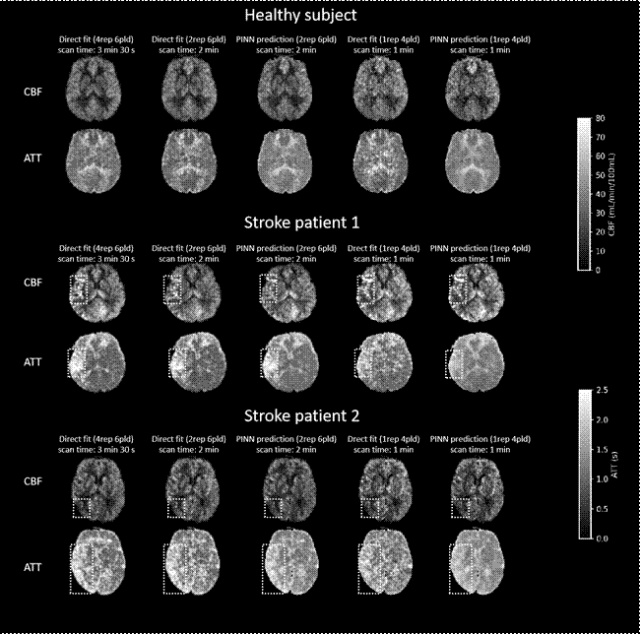

研究团队利用5T超高场磁共振的高信噪比,结合物理信息神经网络(PINN),将动脉自旋标记(ASL)扫描时间从3.5分钟大幅缩短至1分钟(单次采集+4个PLD),同时保持诊断所需的图像质量与定量精度。ASL无需造影剂,对中风、阿尔茨海默病等具有重要价值,但因信噪比低,传统方法需多次采集和多PLD,限制临床应用。新方法峰值信噪比(PSNR)、组内相关系数(ICC)及病灶检测方面均显著优于传统非线性拟合方法,展现出ASL迈向大规模临床应用的巨大潜力。

健康志愿者和中风病人在不同采集时间下使用直接拟合和PINN拟合的脑血流量(CBF)和动脉到达时间(ATT)定量图